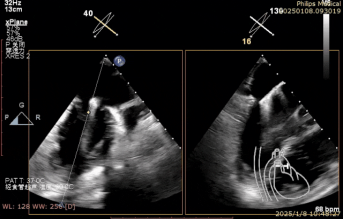

术中房间隔穿刺

术中二尖瓣夹系统瓣上调整

术中二尖瓣夹系统进入瓣下并捕获瓣叶

术中二尖瓣夹系统释放完毕